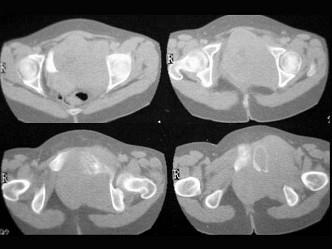

问题 患者,女,54岁,因反复左髋、左下肢疼伴左下肢活动障碍约半年,请结合所提供的图像,选择最佳选项 ( )

选项 A、Ewing肉瘤 B、骨巨细胞瘤 C、滑膜肉瘤 D、骨转移瘤 E、骨髓瘤

答案 A